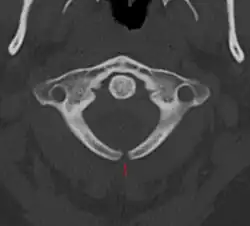

Spina bifida occulta

Часто эта форма называется «скрытое расщепление позвоночника», так как при этом спинной мозг и нервные корешки в норме, а также отсутствует дефект в области спины. Данная форма характеризуется лишь небольшим дефектом или щелью в позвонках, которые формируют позвоночный столб. Зачастую эта форма патологии настолько умеренно выражена, что не вызывает каких-либо беспокойств. При этом такие больные даже не знают о наличии у себя этого порока развития и узнают об этом лишь после рентгенографии. Чаще всего эта форма патологии возникает в пояснично-крестцовом отделе позвоночника. У 1 из 1000 больных могут отмечаться проблемы с функцией мочевого пузыря или кишечника, боли в спине, слабость мышц ног и сколиоз.